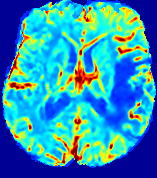

LesionRefer to captionRefer to captionRefer to captionRefer to captionRefer to captionRefer to caption𝐕rgbsubscript𝐕𝑟𝑔𝑏{\bf{V}}_{rgb}Refer to captionRefer to captionRefer to captionRefer to captionRefer to captionRefer to caption𝐕2subscriptnorm𝐕2{\|\bf{V}}\|_{2}Refer to captionRefer to captionRefer to captionRefer to captionRefer to captionRefer to captionRefer to caption3.53.53.52.82.82.82.12.12.11.41.41.40.70.70.70.00.00.0(mm/s)𝑚𝑚𝑠(mm/s)D𝐷DRefer to captionRefer to captionRefer to captionRefer to captionRefer to captionRefer to captionRefer to caption0.0200.0200.0200.0160.0160.0160.0120.0120.0120.0080.0080.0080.0040.0040.0040.0000.0000.000(mm2/s)𝑚superscript𝑚2𝑠(mm^{2}/s)Slice #1Slice #2Slice #3Slice #4Slice #5Slice #6

Figure 4: PIANO feature maps for another patient in the ISLES 2017 training set, where the lesion is located in the right hemisphere. Top row: segmented stroke lesion region (white) on different slices. The corresponding slices for the PIANO feature maps are shown in the following rows.

For a better insight into an estimated velocity field 𝐕𝐕{\bf{V}} and diffusion field 𝐃𝐃{\bf{D}}, we compute the following maps: (1) 𝐕rgbsubscript𝐕𝑟𝑔𝑏{\bf{V}}_{rgb}: Color-coded orientation map of 𝐕=(Vx,Vy,Vz)T𝐕superscriptsuperscript𝑉𝑥superscript𝑉𝑦superscript𝑉𝑧𝑇{\bf{V}}=(V^{x},V^{y},V^{z})^{T}, obtained by normalizing 𝐕𝐕{\bf{V}} to unit length and mapping its 3 components to red, green, blue respectively; (2) 𝐕2subscriptnorm𝐕2\|{\bf{V}}\|_{2}: 222 norm of 𝐕𝐕{\bf{V}}; (3) D𝐷D: scalar field in Eq. 5.

Fig. 3 and Fig. 4 show the PIANO feature maps estimated from two ISLES 2017 patients: all are highly consistent with the lesion in both cases. Details of the blood flow trajectories are revealed in 𝐕rgbsubscript𝐕𝑟𝑔𝑏{\bf{V}}_{rgb} by the ridged patterns and the sharp changes of colors in the unaffected (right) hemisphere, while the flat patterns appearing within the lesion provide little directional information about the velocity and indicate low velocity magnitudes. Velocity magnitudes are more directly visualized via 𝐕2subscriptnorm𝐕2\|{\bf{V}}\|_{2}, from which one can easily locate the lesion where 𝐕2subscriptnorm𝐕2\|{\bf{V}}\|_{2} is low. D𝐷D also indicates lower diffusion values in the lesion, though with less contrast potentially due to the fact that it captures the accumulated effect of CA diffusion at the voxel-level.